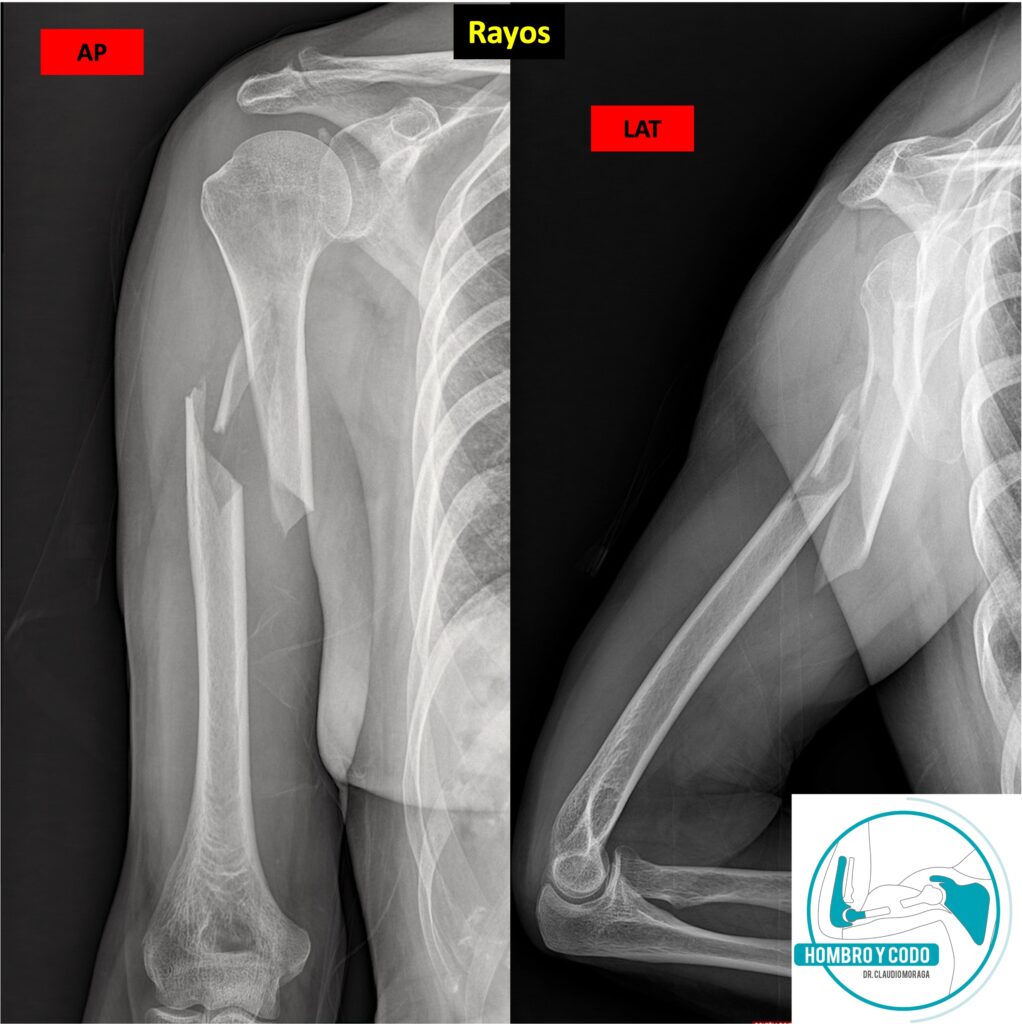

– Radiografías: Las proyecciones básicas son la Anteroposterior (AP) y lateral del húmero, las que siempre deben incluir hombro y codo para descartar lesiones de estas articulaciones vecinas (Fig 03).